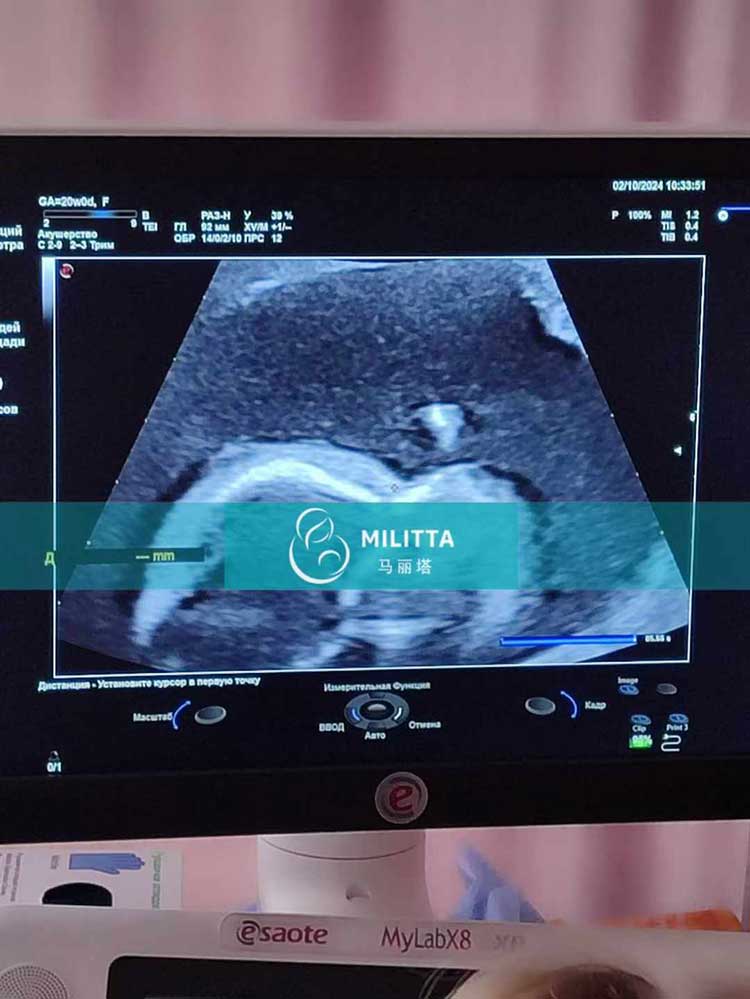

格鲁吉亚客户的三位爱心妈妈来医院做孕20周的B超产检

陪同格鲁吉亚客户的三位爱心妈妈来医院做孕20周的B超产检,其中两位乌克兰试管妈妈在基辅做的,一位哈萨克斯坦试管妈妈在第比利斯做的,胎儿都发育良好